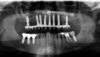

Cas 2: Vues panoramiques

AVANT REHABILITATION

PENDANT REHABILITATION 3 SECTEURS MOLAIRES

APRES REHABILITATION 3 SECTEURS MOLAIRES